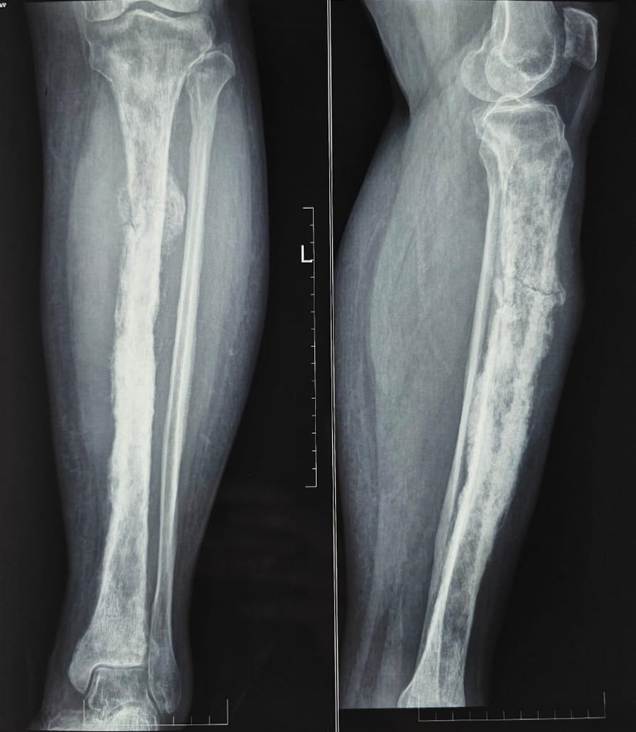

Baseline blood investigations revealed hemoglobin 12 g/dL, leukocyte count 5,000/mm3, platelets 210,000/mm3, erythrocyte sedimentation rate 30 mm/h, and C-reactive protein 5.8 mg/L. Radiographs of the left tibia showed a mixed lytic–sclerotic lesion with cortical breach and periosteal reaction (Fig. 2). Magnetic resonance imaging demonstrated an ill-defined metaphyseal lesion with marrow replacement, cortical destruction, soft-tissue extension, and pathological fracture (Fig. 3). Core needle biopsy suggested a hematolymphoid malignancy, confirmed by open biopsy showing diffuse large atypical lymphoid cells (Fig. 4). Immunohistochemistry revealed diffuse CD45 and CD20 positivity, scattered CD3 positivity, and high Ki-67 (~60%) with cytokeratin negativity (Fig. 5). Positron emission tomography-computed tomography (PET-CT) revealed an avid mass in the proximal tibia with metabolically active regional nodes. Cultures were sterile.

Figure 2: Anteroposterior (a) and lateral (b) radiographs of the left proximal tibia at presentation, demonstrating a lytic, expansile lesion with cortical thinning and breach along the medial cortex, associated with periosteal reaction and surrounding soft-tissue shadow. Findings are consistent with an aggressive destructive process involving the metaphyseal region.